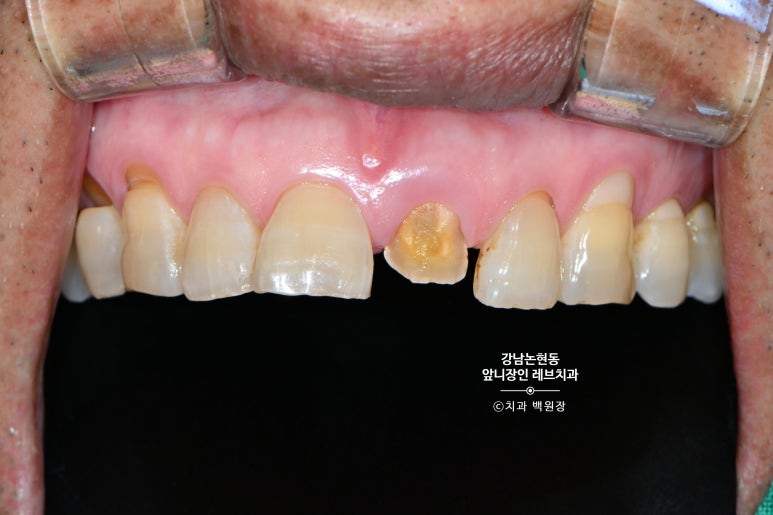

60대 남자 환자분이 저희 치과에 내원하셨습니다.

앞니가 부러져서 오신거에요.... 생니가 그냥 부러져 버렸습니다.

아마 씹는 힘도 세시고, 물리는 형태도 깊게 물리는 형태셔서 앞니가 너무 큰 힘을 받았을겁니다.

누적된 외력에 어느날 치아가 부러져 버린거죠.

윗니 아랫니 공간을 보시면, 치아가 얼마나 부러질만한 힘을 받았을지 상상해볼 수 있습니다..

고생했을 앞니.. 환자분은 다른 치과에서 뽑고 임플란트 해야한다는 설명을 듣고 살릴 수 없는지 문의해보러 오셨습니다.